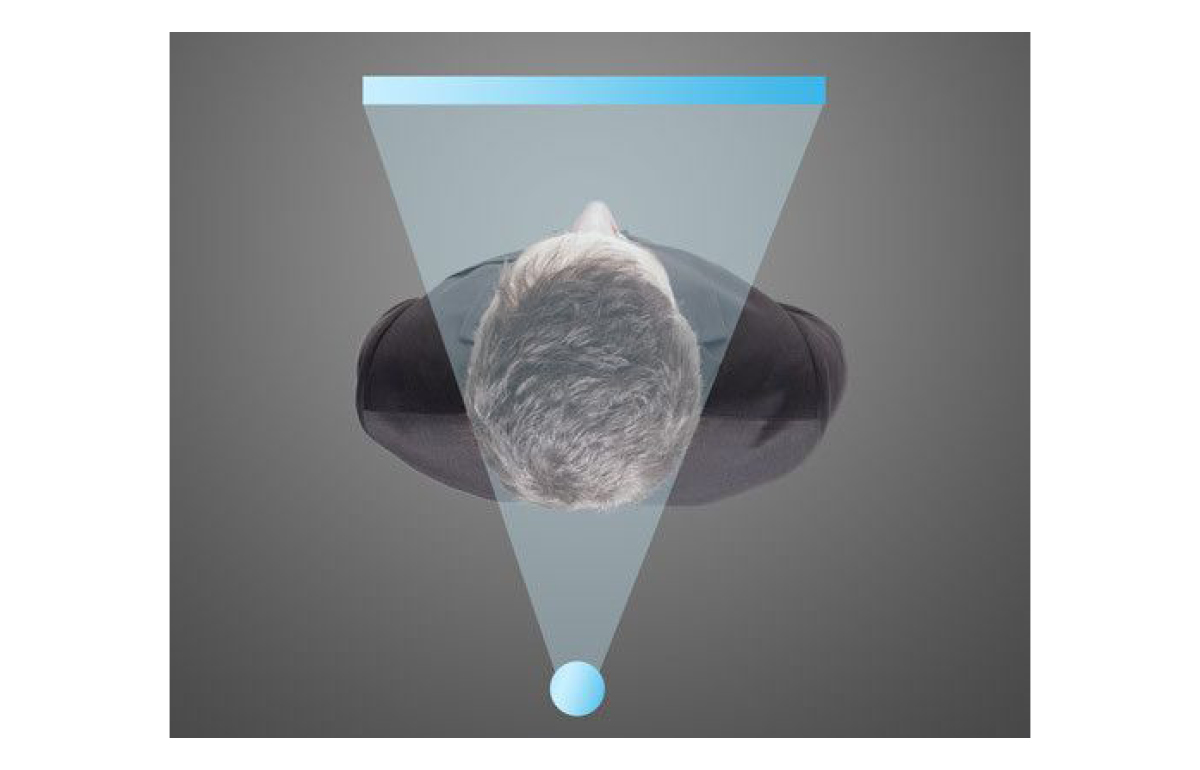

Seated Position

i-CAT FLX is one of the few machines that provide a seated position for scanning. Ergonomic Stability System (ESS) allows for easy seated patient positioning, designed to minimize patient movement and avoid unnecessary retakes and additional radiation.